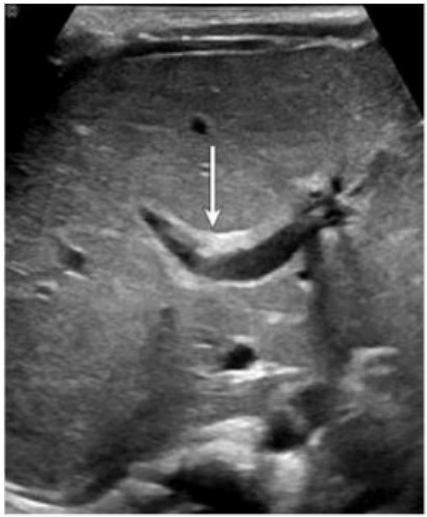

Which congenital disorder is most consistent with the finding identified by the arrow on this image?

The image demonstrates a characteristic 'central dot sign' --- a hallmark finding of Caroli disease. This is best appreciated on ultrasound as a cystic dilation of the intrahepatic bile ducts with a central echogenic dot or linear structure (which corresponds to the portal vein and fibrous tissue within the dilated duct). The arrow in the image points to one such dilated duct.

Caroli disease is a rare congenital disorder characterized by segmental, saccular dilation of intrahepatic bile ducts. It is often associated with congenital hepatic fibrosis and may predispose to cholangitis, stone formation, and even cholangiocarcinoma.

Key ultrasound features of Caroli disease:

Cystic or saccular dilations of the intrahepatic bile ducts

The 'central dot sign' --- echogenic focus in the center of the dilated ducts (representing portal vein radicle or fibrous tissue)